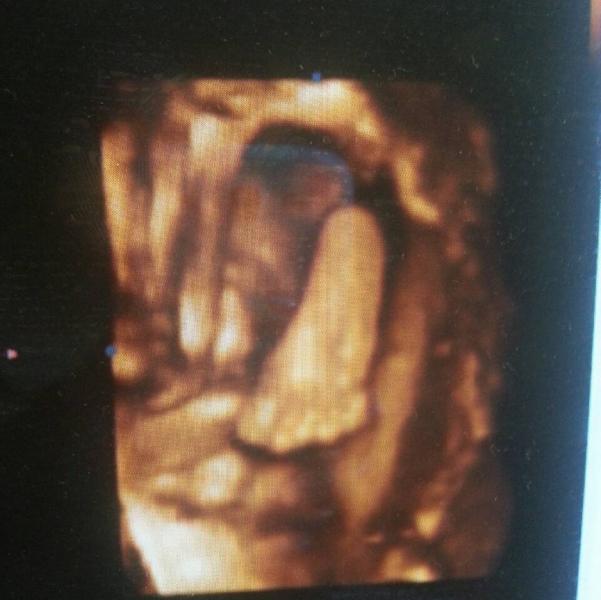

Сегодня сходили на 3д узи тьфу-тьфу у нас все отлично дочя весит 1400 , безумно рада скорее бы встретиться со своей малышкой!!!

@alename195, в принципе, засняли, вместе с ручкой))) закрывалась все узи) пол-лица засняли))) наша хмурилась, не нравилось, что снимали и дергали постоянно чтоб личико показала 😅 с характером)